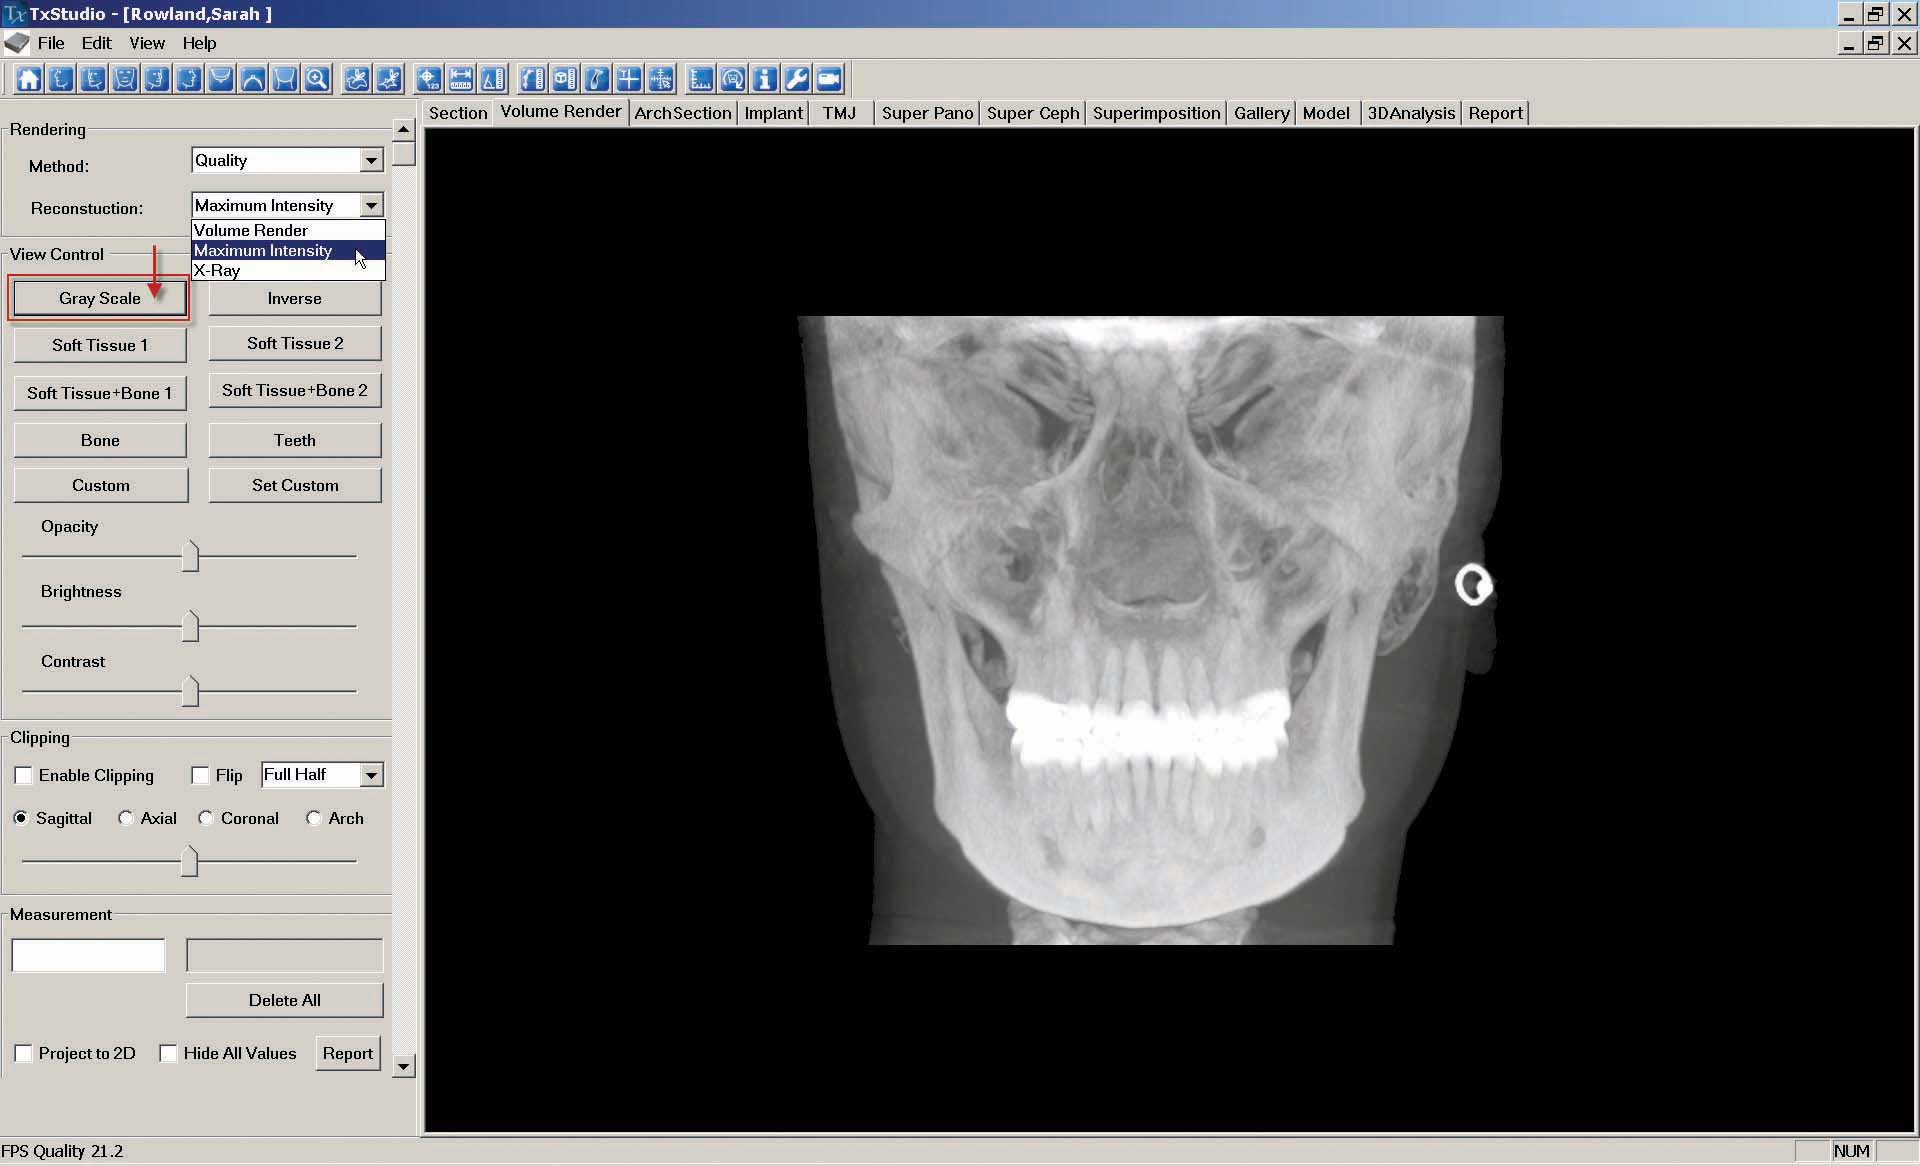

a. To create the "Hard Frontal" image, go to the "Volume Render" tab. On the upper left side of the screen, select "Maximum Intensity" from the "Reconstruction" drop-down menu and then select "Gray Scale."

As described in step 7, "Capture to Gallery" and name the image "Hard Frontal."